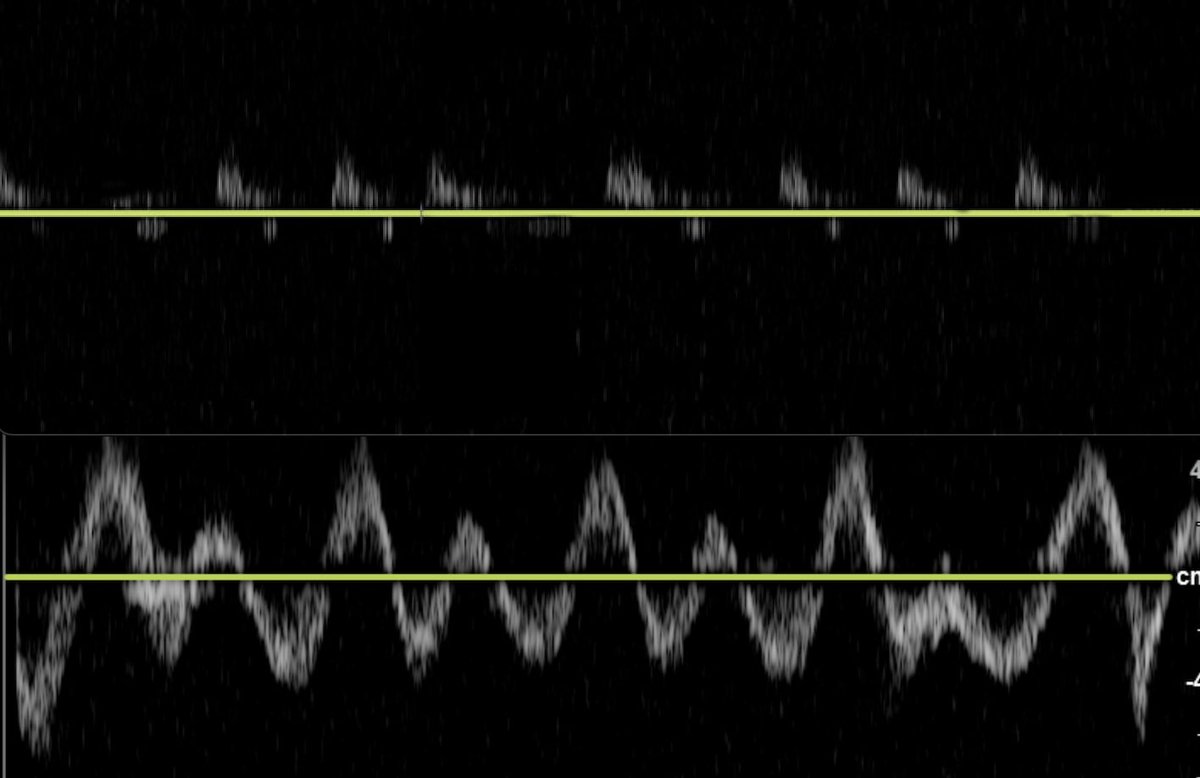

Another HV Doppler:

S Wave reversal better seen here. Thanks to @ArgaizR

S Wave reversal better seen here. Thanks to @ArgaizR